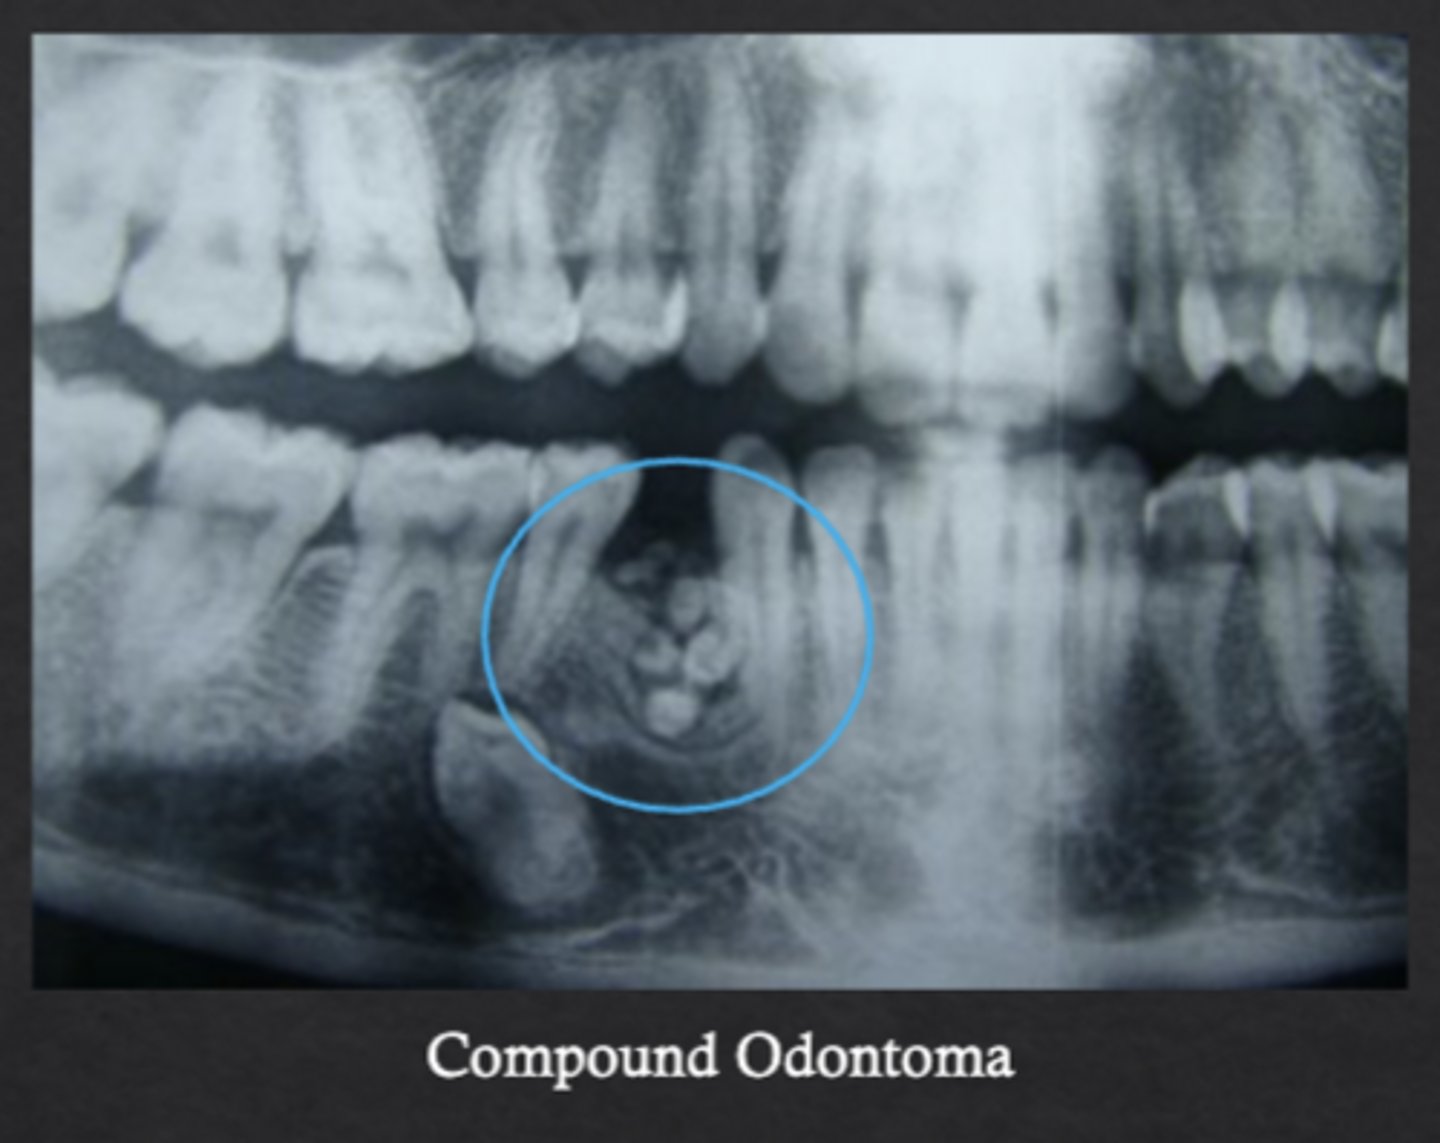

What is an odontoma?

Benign odontogenic tumor composed of enamel, dentin, cementum, and pulp

What is a compound odontoma?

Forms multiple small tooth-like structures with recognizable layers of dental antomy

What is a complex odontoma?

Disorganized mass of dental tissues without a tooth-like form